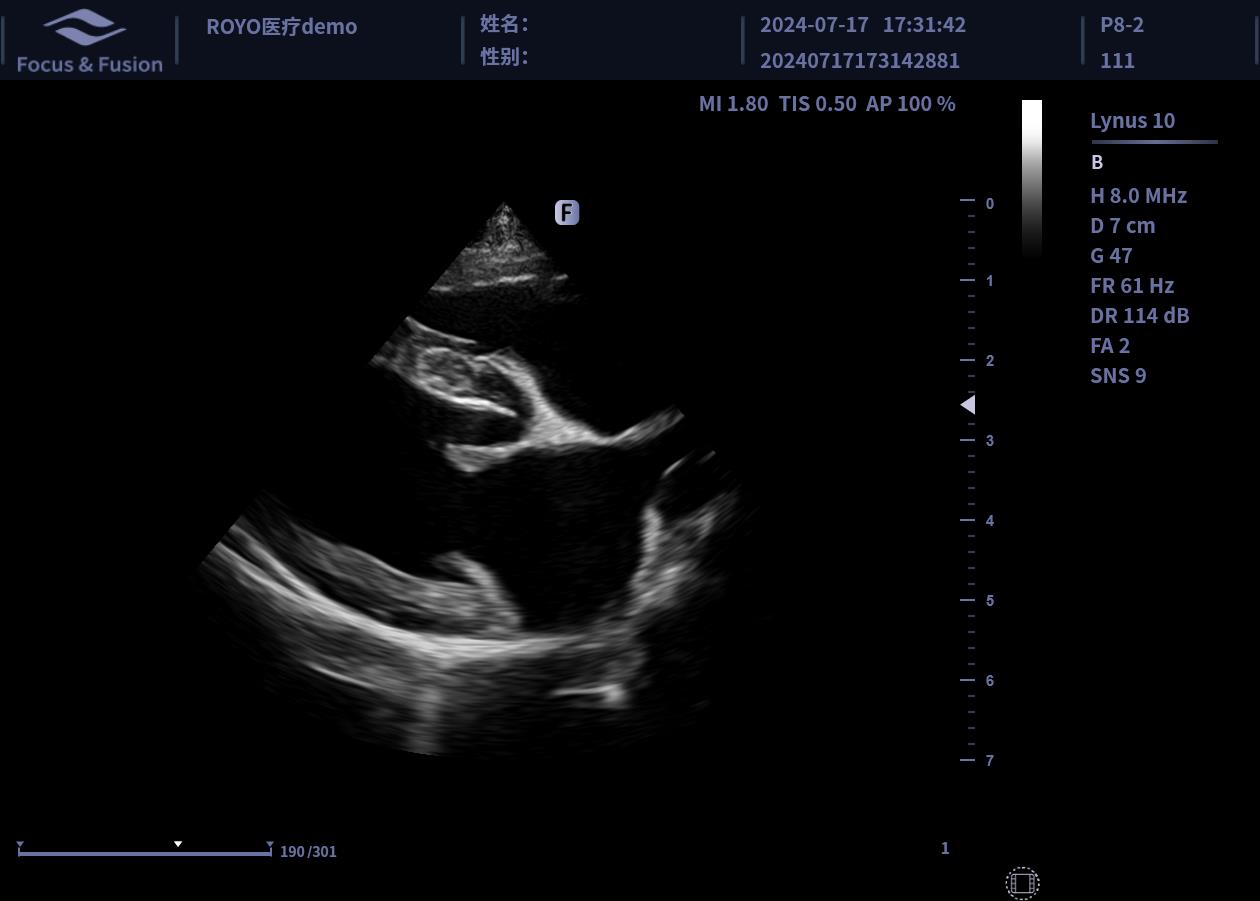

圖片展示

Image List